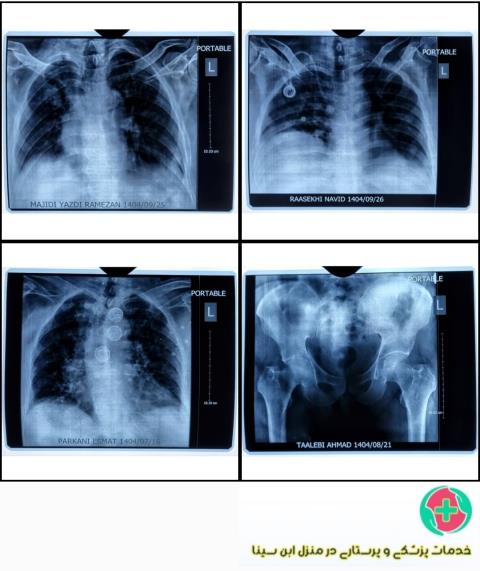

رادیولوژی لگن و ران و فمور در منزل:

اگر با مشکلات مربوط به لگن و ران روبهرو هستید، میتوانید از خدمات رادیولوژی در منزل بهره ببرید. با استفاده از تجهیزات پیشرفته و فناوری روز، میتوان عکسهای رادیولوژیک از این قسمتهای بدن در منزل گرفت و به پزشک نشان دهید. این کار به شما کمک میکند تا به سرعت تشخیص دقیقی از وضعیت سلامتی خود بگیرید و برنامه درمانی مناسب را شروع کنید.

رادیولوژی ریه و قفسه سینه و شکستگی دنده در منزل:

مشکلات مربوط به ریه و قفسه سینه از جمله عفونتها، سرطانها و بیماریهای تنفسی میتوانند جدی باشند و نیازمند تشخیص سریع و دقیق هستند. با استفاده از رادیولوژی در منزل، شما میتوانید تصاویر پرتویی از این بخشهای بدن را در محیط آرام منزل گرفته و به پزشک نشان دهید تا در تشخیص و شروع بهتر درمان کمک کننده باشد.